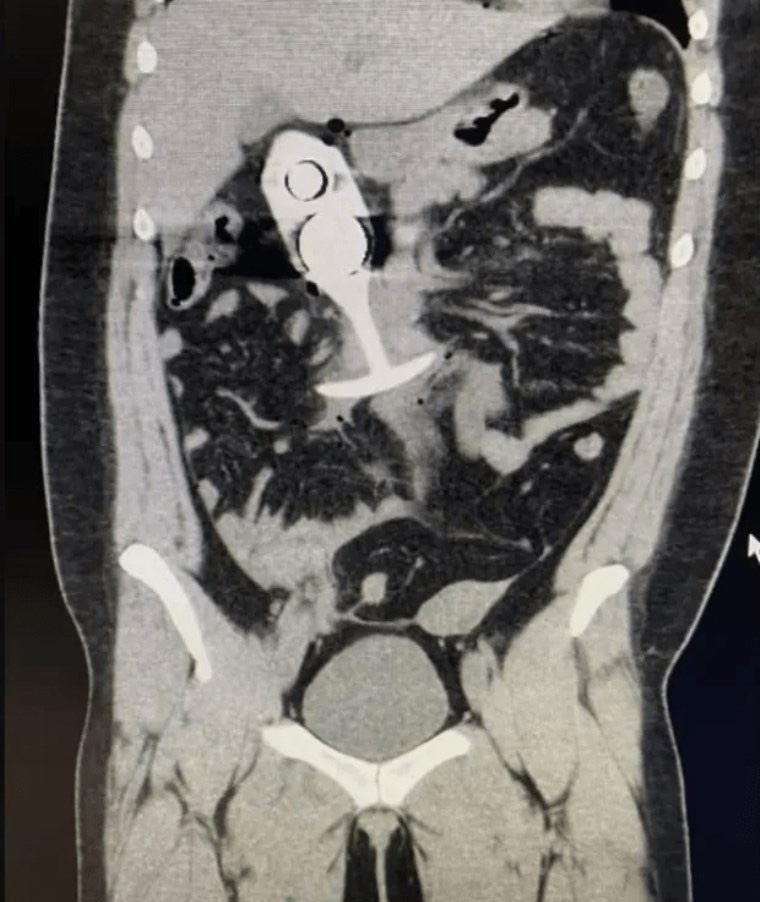

Yüzde 100 silikon olduğunu düşündüğü seks oyuncağı makatında taramaya giren genç kadın, oyuncağın çekirdeğinde metal bulunduğu anlaşılınca büyük tehlike yaşadı.

Taramadan sonra, hasta şiddetli ağrı hissetti ve bilincini kaybedecek kadar kötüleşti. Oyuncak, hastanın vücudunun alt kısmından yukarı doğru hareket ederek ciddi iç yaralanmalara neden oldu. Sağlık ekipleri tarafından hemen hastaneye kaldırılan kadın, ciddi yaralar almasına karşın hayati tehlikeyi atlattı.